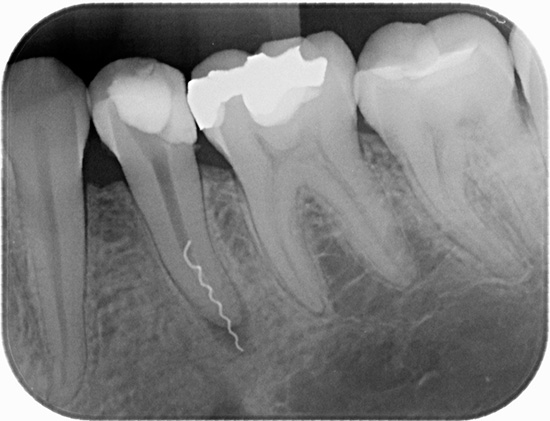

- immagine di controllo (radiografia).

Un microscopio in endodonzia viene utilizzato, in particolare, per diagnosticare il numero di canali radicolari e la qualità del loro passaggio. Il trattamento della pulpite di un dente a tre radici al microscopio consente di trovare e trattare rapidamente anche i passaggi più difficili e ci sono molti casi simili nella pratica di un dentista.

Un microscopio endodontico ci consente di dire con quasi il 100% di certezza alla fine del trattamento che tutti i canali sono stati passati e correttamente sigillati. È lui che ti consente di controllare ogni fase del trattamento della pulite, prevenendo ulteriori complicazioni. Il trattamento tradizionale senza l'uso di un microscopio è spesso associato alla presenza di conseguenze negative a lungo termine, ad esempio a causa del fatto che il medico semplicemente non ha potuto vedere il canale aggiuntivo nel dente e lo ha perso durante il trattamento, lasciando una polpa infetta al suo interno.

A volte, durante il trattamento della pulpite, il medico trova 3 canali, ma in realtà c'è un quarto canale (o addirittura un quinto) "ben nascosto" nel dente. Ci sono casi in cui non manca un canale, ma diversi, poiché ci sono opzioni complesse per la loro posizione nel dente.